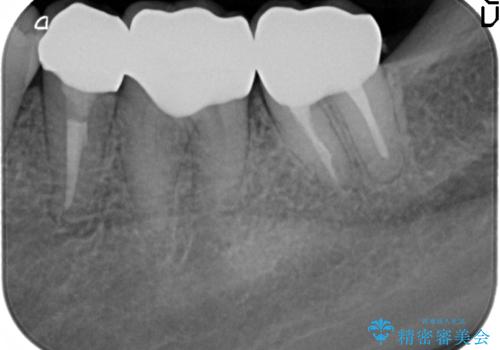

現在装着されているクラウンを除去したところ、クラウンマージンが歯肉縁下となり歯ぐきの炎症が認められたため再度オールセラミッククラウンを製作する前に歯周外科手術を行い歯ぐきの状態を改善しました。

- 45万円(仮歯×3・ファイバーコア×2・ジルコニアクラウン×3 歯周外科手術)費用は治療当時の料金となります